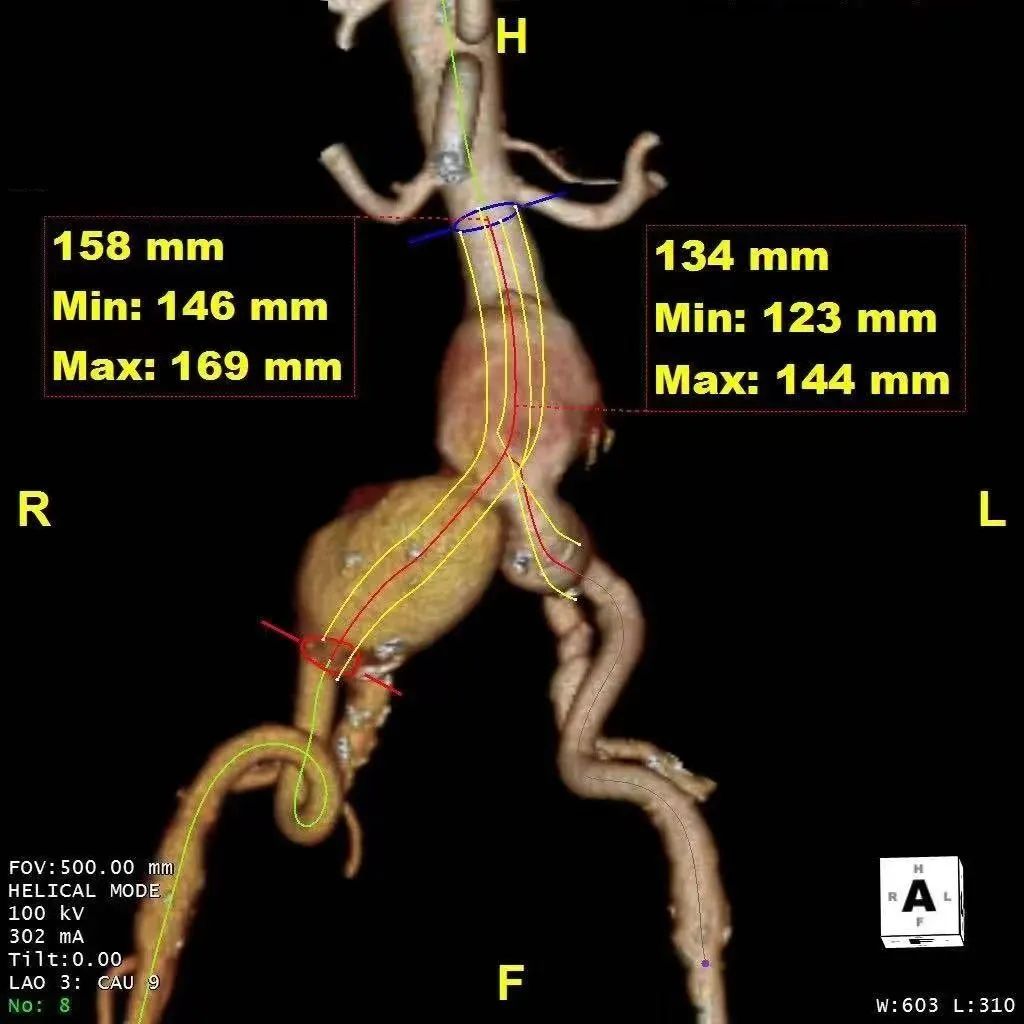

该病例系67岁的老年患者,诊断:腹主动脉瘤、双侧髂动脉瘤、瘤体内伴有附壁血栓。病变解剖复杂,且累及双髂内动脉,为术者团队提出诸多挑战,而该患者既往因胸主动脉疾病已行胸主动脉腔内修复(TEVAR)+左锁骨下动脉(LSA)原位开窗重建术,治疗挑战不断升级。团队需要认真思考讨论并解决诸多的难点:1.完全隔绝腹主动脉及髂动脉病变;2.如何避免因胸腹主动脉长段隔绝后的截瘫风险;3.如何解决LSA原位开窗后手术入路受限问题。

手术团队为此进行了多次的病例手术方案讨论,从器械的选择、入路的解决到辅助技术的应用,都予以详细的分析并制定相应的预案。最终确定了以IBE+3D影像融合引导下保右侧髂内动脉的EVAR术。基于详尽而充分的术前准备,手术如期而顺利进行,术者通过娴熟的腔内介入技术克服诸多困难,2小时内顺利完成手术,微创的腔内介入使术中出血量不足20ml。患者术后快速恢复,5天后康复出院。

术前方案示意图